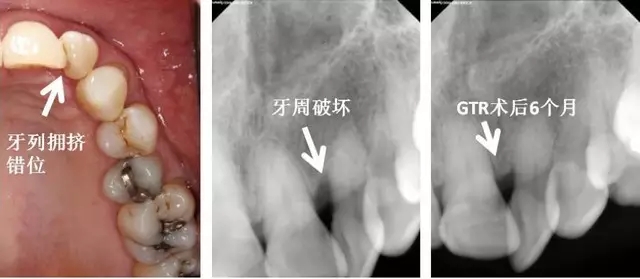

牙列因素

1. 牙列擁擠

2. 牙列不整齊

3. 咬合錯(cuò)位

左上側(cè)切牙扭轉(zhuǎn),牙列擁擠,造成口腔衛(wèi)生困難,牙周破壞。告知患者牙列擁擠應(yīng)該予以治療以去除危險(xiǎn)因子,再進(jìn)行牙周手術(shù)?;颊卟辉敢庹委?,選擇直接牙周手術(shù)。告知患者需要高質(zhì)量口腔衛(wèi)生,并且需要更為頻繁的專業(yè)清潔。